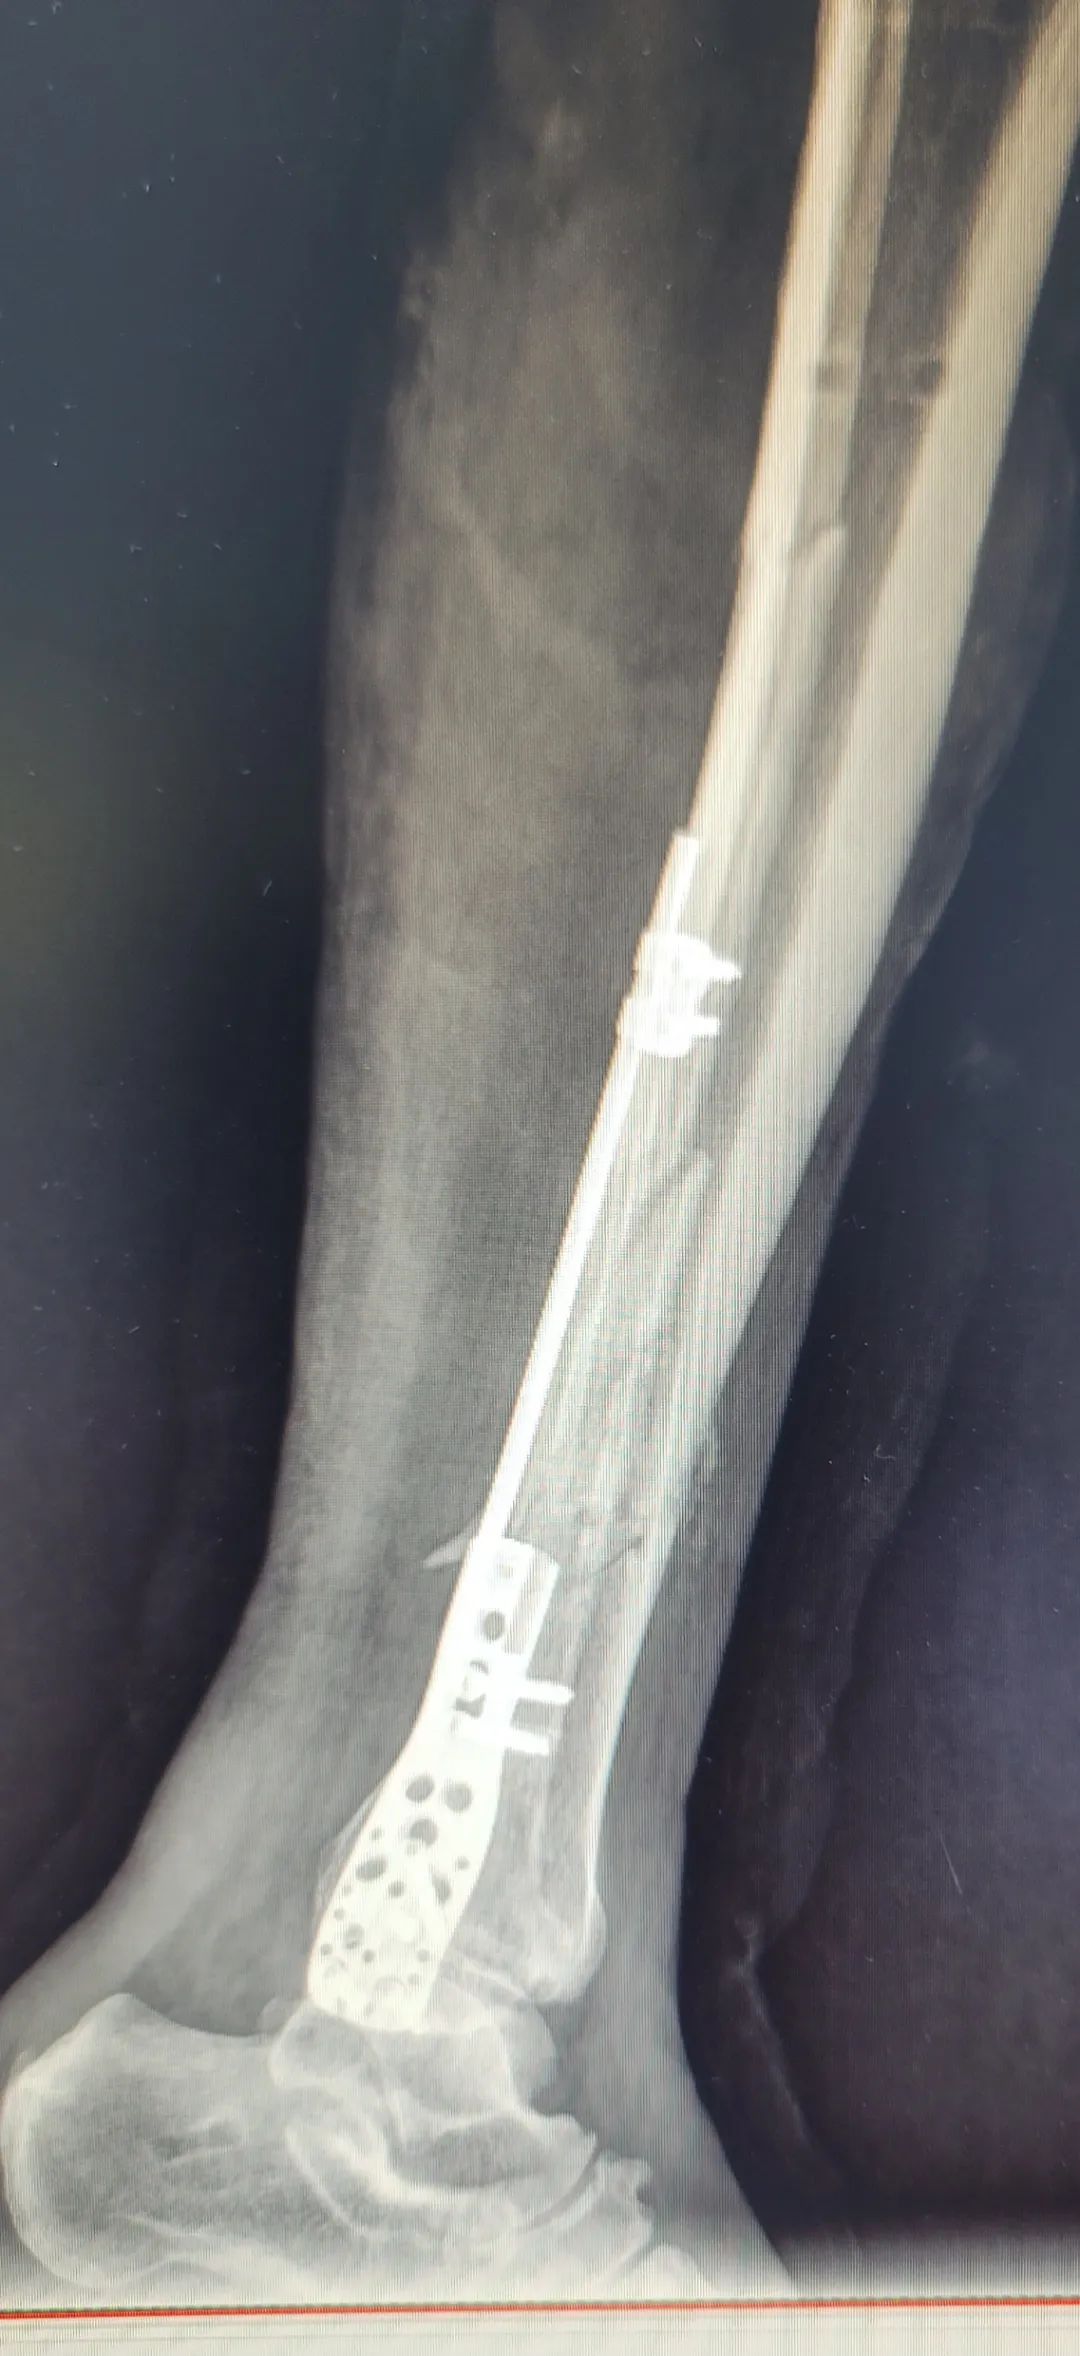

鉴于患者手术后左小腿皮肤形成了大面积溃疡创面,小腿骨折合并溃疡创面是一种复杂且具有挑战性的骨科疾病,传统的治疗方法通常采用常规钢板进行手术,但存在钢板外露的风险,增加康复难度。骨外科三区手术团队经过深入研究和反复探索,认为桥接钢板单杆模块由高强度钢材制成,具有良好的稳定性和可塑性,单杆通过溃疡区域时不容易激惹皮肤。在取得患者及其家属的信任后,创新性地采用了桥接钢板单杆模块为患者进行微创手术,手术最终得以顺利完成。患者术后创面愈合良好,无钢板外露的情况发生。

我院骨外科三区桥接钢板单杆模块的成功应用,具有更好的适应性和稳定性,有效减少钢板外露的风险,为小腿骨折合并溃疡创面手术提供了新的选择,将在复杂创面骨科手术中发挥更大的作用。